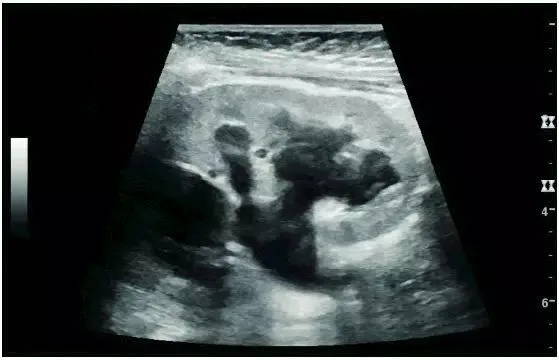

Hydronephrosis in children can be caused by obstruction of the ureteropelvic junction, ectopic ureteral orifice, primary megaureter, and posterior urethral valves (below). In adults, hydronephrosis can be caused by urolithiasis, obstruction of the renal pelvis or ureter, and ureteral compressions, such as pregnancy and retroperitoneal fibrosis. Urolithiasis is the most common cause of hydronephrosis in adults, with a prevalence of 10%-15%.

Hydronephrosis due to obstruction of the ureteropelvic junction in children